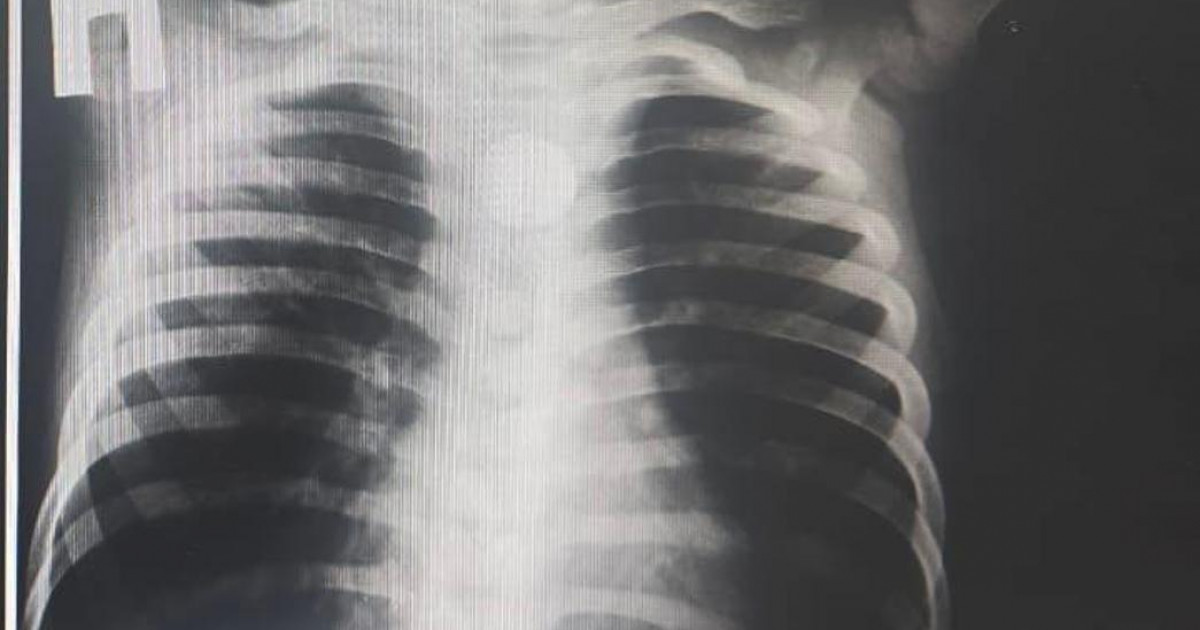

Жүкті болғанына 23 апта болған науқасқа «екіншілік жүрекшеаралық қалқа ақауы» диагнозымен жергілікті жансыздандыру арқылы хирургиялық ота жасалды. Бұл әдіс ана мен ұрыққа рентгенмен сәулелену қаупін болдырмайды.